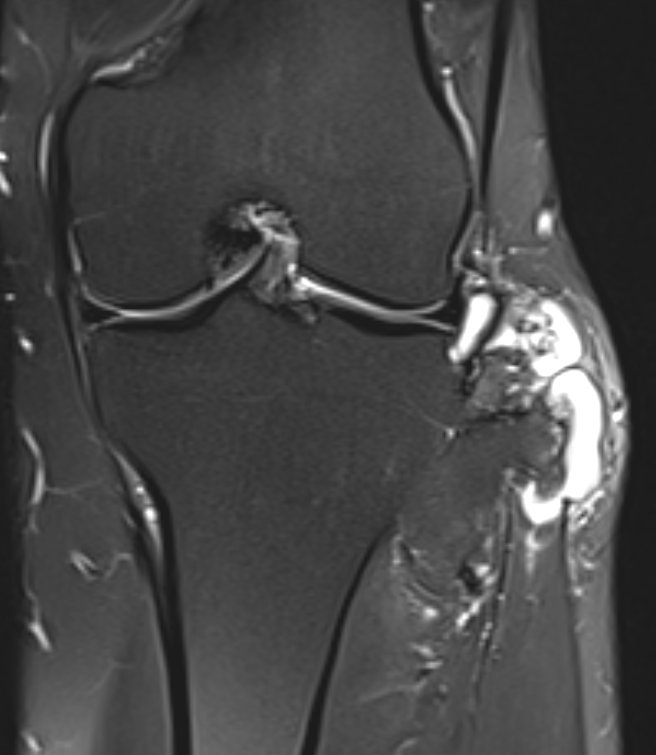

MRI

- MRI of 179 chondrosaroma

- features of high grade chondrosarcoma

- bone expansion, active periostitis, soft tissue mass and increased tumour length